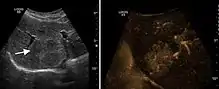

Hepatic hemangioma (2D). The lesion is located in the left hepatic lobe. Note precise delineation, their increased echogenity and the heterogeneous internal structure.

Hepatic hemangioma (CEUS). Progression of CA from the periphery toward the center of the lesion is evidenced by examination at various time intervals (a – arterial phase; b – late phase).

It is the most common liver tumor with a prevalence of 0.4 – 7.4%. It is generally asymptomatic but also can be associated with pain complaints or cytopenia and/or anemia when it is very bulky. It is unique or paucilocular. It can be associated with other types of benign liver tumors. Characteristic 2D ultrasound appearance is that of a very well defined lesion, with sizes of 2–3 cm or less, showing increased echogenity and, when located in contact with the diaphragm, a "mirror image" phenomenon can be seen. When palpating the liver with the transducer the hemangioma is compressible sending reverberations backwards. Doppler exploration reveals no circulatory signal due to very slow flow speed. CEUS investigation has real diagnosis value due to the typical behavior of progressive CA enhancement of the tumor from the periphery towards the center. The enhancement is slow, during several minutes, depending on the size of hemangioma and on the presence (or absence) of internal thrombosis. During late (sinusoidal) phase, if totally "filled" with CA, hemangioma appears isoechoic to the liver. Deviations from the above described behavior can occur in arterialized hemangiomas or those containing arterio-venous shunts. In these cases, differentiation from a malignant tumor is difficult and requires other imaging procedures, follow up and measurements of the tumor at short time intervals.[4]

Benign focal nodular hyperplasia (CEUS). Gray scale examination (left) detects the lesion. CEUS examination (right) allows characterization of tumor nature based on central contrast enhancement and centrifugal dispersion.

It is a tumor developed secondary to a circulatory abnormality with abundant arterial vessels having a characteristic location in the center of the tumor, within a fibrotic scar. A radial vessels network develops from this level with peripheral orientation. The tumor's circulatory bed is rich in microcirculatory and portal venous elements. The incidence is higher in younger women and tumor development is accelerated by oral contraceptives intake. 2D ultrasound appearance is a fairly well-defined mass, with variable sizes, usually single, solid consistency with inhomogeneous structure. Rarely the central scar can be distinguished. Spectral Doppler examination detects central arterial vessels and CFM exploration reveals their radial position. CEUS examination shows central tumor filling of the circulatory bed during arterial phase and completely enhancement during portal venous phase. During this phase the center of the lesion becomes hypoechoic, enhancing the tumor scar. During the late phase the tumor remains isoechoic to the liver, which strengthens the diagnosis of benign lesion.